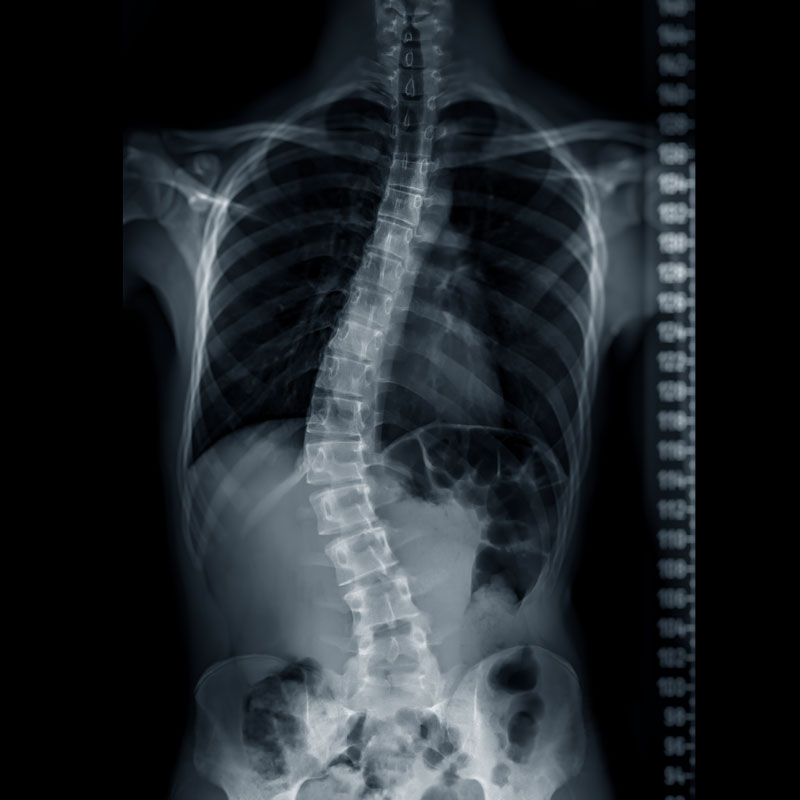

Scoliosis

Scoliosis can lead to a variety of symptoms, including back pain, muscle imbalance, uneven shoulders, and restricted mobility. Left untreated, it may progress over time, causing more severe spinal deformities and complications.

Types of Scoliosis

- Idiopathic Scoliosis: The most common type, often diagnosed in adolescents, with no identifiable cause.

- Congenital Scoliosis: Present at birth due to abnormal spinal development in the womb.

- Neuromuscular Scoliosis: Associated with conditions such as cerebral palsy or muscular dystrophy that affect the muscles and nerves.

- Degenerative Scoliosis: Often seen in adults due to age-related wear and tear, including arthritis or disc degeneration.

- Functional Scoliosis: Caused by temporary issues such as muscle spasms or leg length discrepancies.